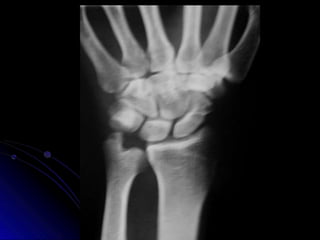

MUÑECA PA

Estructuras Visualizadas

•Metacarpianos 1-5

•Carpianos - Escafoides,

Semilunar, Piramidal,

Pisiformes, Trapezio,

Trapezoides, Hueso Grande,

Ganchoso

•Cubito

•Estiloides Cubital

•Radio

MUÑECA PA - MARCADO